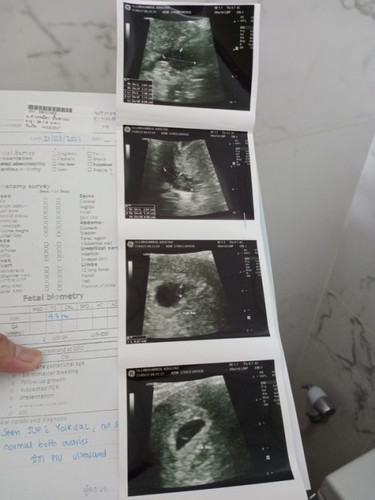

พี่ๆเจอถุงตั้งครรภ์และไข่แดงตอนกี่วิคกันคะบ้านนี้7วิคยังไม่เจอตัวอ่อนน้องเลยคะเจอแต่ถุงตั้งครรภ์และใข่แดงหนูกังวนมากเลยคะ

ไม่เจอน้องเหมือนกันค่ะ7วีค4วันซาวช่องคลอดก็ไม่เหน

บ้านนี้เจอตัวน้อง 8w ค่ะ